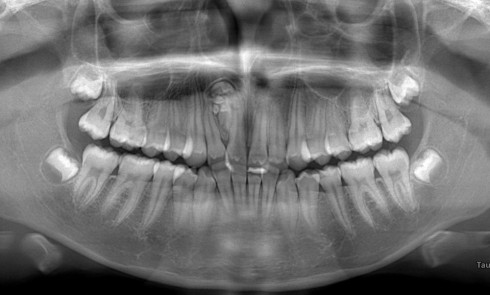

Article réservé à nos abonnés Prise en charge occluso-prothétique des conséquences orales et maxillo-faciales du bruxisme : apport de la prothèse amovible de recouvrement

Le bruxisme est défini comme le grincement parafonctionnel des dents, ou encore comme une habitude orale composée de tapotements, de...